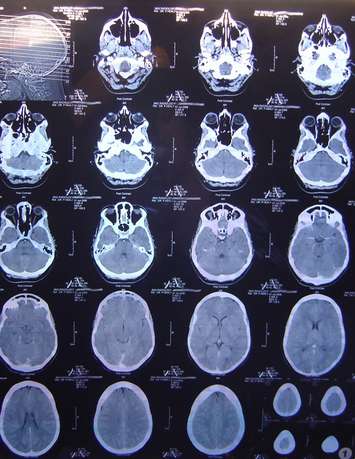

CT Scan (Image courtesy of missellie via Flickr)CT Scan (Image courtesy of missellie via Flickr)

Windsor Regional Hospital (WRH) announced Saturday that there will be a postponement of non-emergency CT scans, cardiac angiograms, and diagnostic studies until at least the end of June.

The hospital said that it was alerted of an international shortage of a solution known as iodinated contrast dye which is used in diagnostic imaging on Friday.

The dye WRH uses is supplied by GE Healthcare, which has four global manufacturing sites, one of which was recently forced to shut down due to COVID-19 concerns. The plant has re-opened, but it's expected to take several weeks for the production of the dye to return to full capacity.

As a result, the hospital anticipates it will only receive half of its normal shipments in the coming weeks.